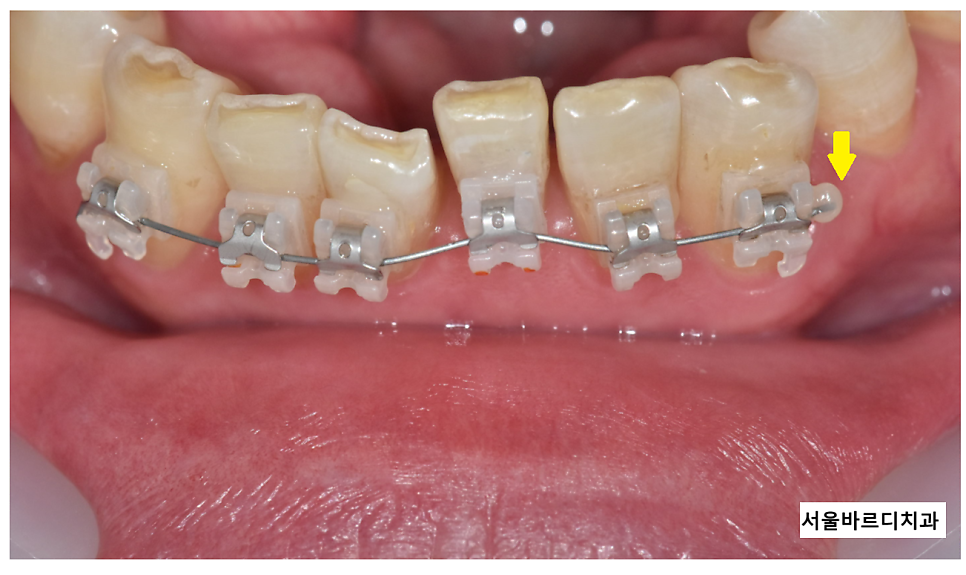

첫번째로 치아 이동으로 철사가 길어졌을 때입니다.

어금니 맨 끝 부분 살이 많이 찔리죠ㅠㅠ

주로 어금니 맨 끝쪽 부분에서 많이 발생해요~

치아가 이동하면서

기존에 딱! 맞게 잘라드린 철사가 바깥으로 빠져나오면서요~

250328 철사가 찔리지 않게 레진을 붙여드리거든요~